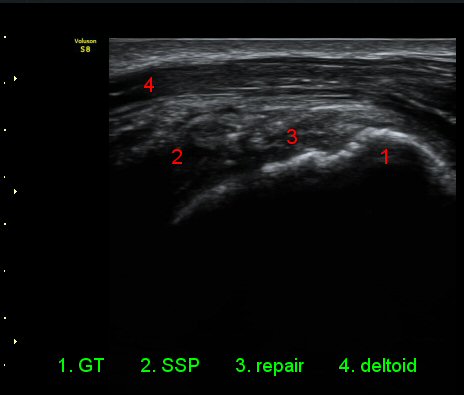

¾î±ú¸¦ ³»Àü, ³»È¸Àü, ½ÅÀüÇÏ¿© ±Ø»ó°Ç°Ë»ç¿¡¼­ ±Ø»ó°Ç ÆÄ¿­ ÈÄ ¼ö¼úÇÑ ¼Ò°ß, ±Ø»ó°ÇÀÇ

Àú¿¡ÄÚ ºÎÁ¾°ú ºÎºÐÀû ÆÄ¿­, °í¿¡ÄÚ ºÀÇÕ»ç, ´ë°áÀýÀÇ ºÒ±ÔÄ¢º¯È­,À» º¸¿©ÁØ´Ù(»çÁø 6, 7, 8, 9)